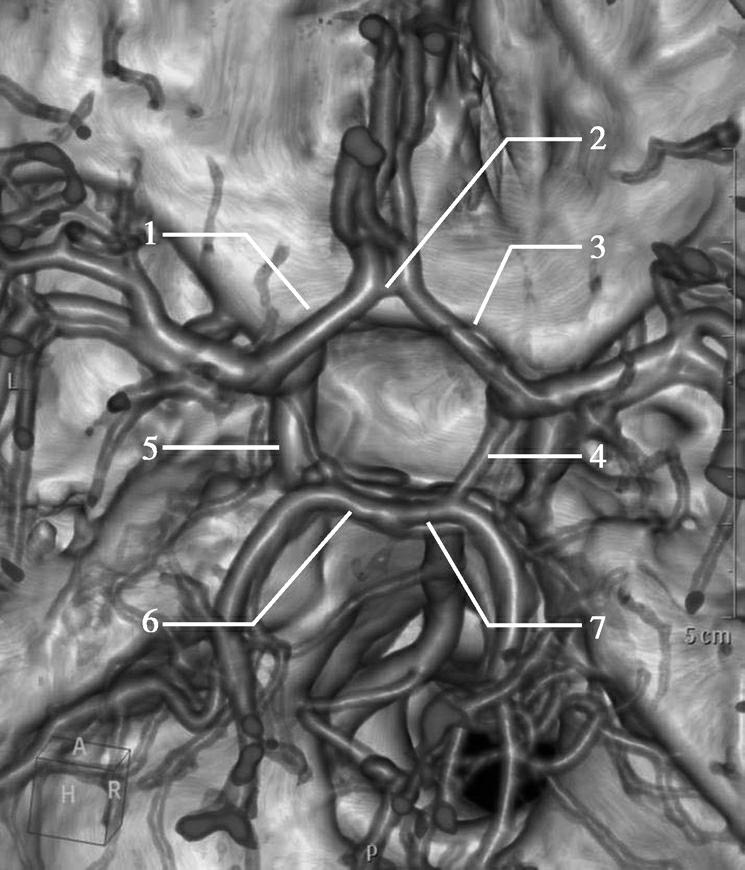

CT血管成像(CT angiography,CTA及CT venography,CTV)通过三维重建技术可显示颅内动静脉的走行、血管壁及血管周围等情况(图1-2-73~图1-2-75)。

图1-2-73 正常颅脑CTA

1.大脑前动脉;2.大脑中动脉;3.颈内动脉;4.大脑后动脉;5.基底动脉;6.椎动脉

大脑动脉环又称Willis环,为连接大脑两半球前部循环及椎基底系统的大吻合环,呈多边形,由下列结构组成:两条大脑前动脉(ACA)交通前段(A 1 ),两侧大脑后动脉(PCA)交通段(P 1 ),两侧颈内动脉(ICA)末端,前交通动脉(ACoA),两侧后交通动脉(PCoA),两侧ICA在脑底通过ACoA相通,并且借PCoA与椎基底动脉系统相通(图1-2-86)。

图1-2-86 正常大脑动脉环

1.左侧大脑前动脉(ACA)交通前段(A 1 );2.前交通动脉(ACoA);3.右侧大脑前动脉(ACA)交通前段(A 1 );4.右侧后交通动脉(PCoA);5.左侧后交通动脉(PCoA);6.左侧大脑后动脉(PCA)交通段(P 1 );7.右侧大脑后动脉(PCA)交通段(P 1 )

大脑动脉环小而重要的穿支血管给许多重要结构供血,如垂体柄、垂体腺、丘脑、下丘脑视神经交叉、视神经、视束、基底节及中脑。对于闭锁性血管疾病,大脑动脉环是侧支血流最充分的供血来源,熟知其正常解剖、变异与异常十分必要。